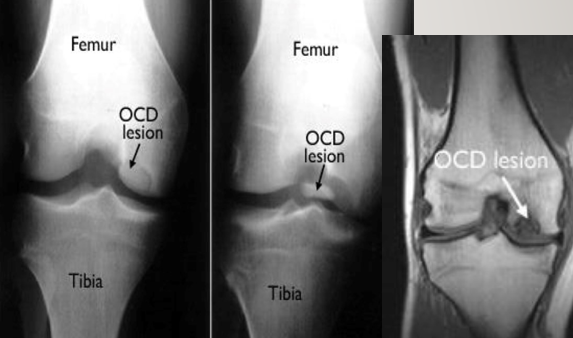

Knee: Osteochondritis Dissecans (OCD)

etiology and common complaints

Etiology:

Subchondral necrosis and collapse with cartilage damage (AVN but on a smaller scale)

Hereditary, traumatic, or vascular in nature

Common symptoms/complaints:

Knee pain with locking/ popping

Knee: Osteochondritis dissecans

PE and test

Physical Exam:

Localize joint line tenderness

Occasionally will have effusion

Occasionally will have popping

Tests: start with X-Rays (knee – notch view) but MRI is needed to determine severity

8

Tx and pearls

Treatment:

Kids: more conservative tx like rest, cast, NWB x several months

Adults: stable – weight bearing restrictions, unstable surgical repair – drilling, screw fixation, resurfacing, joint replacement

Both require surgical removal if there is a loose body in the joint

Pearls:

Most common location of OCD in the knee is the posterior lateral aspect of the medial femoral condyle (70%), capitellum of humerus, talus